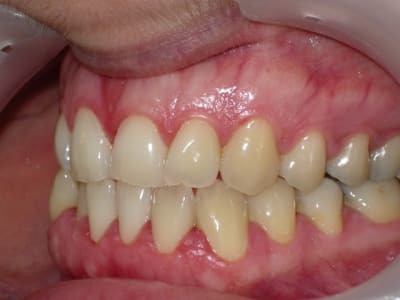

voici de la cas d'un jeune dame de 23 ans qui présente une full classe III subdivision Droite (associée à des compensations incisives de classe III), sur un terrain hyperdivergent. on note un encombrement inferieur d'environ 2 mm et une abrasion des bords triturants des incisives inf (Motif de la consultation)

on notera egalement de face une déviation de la pointe du menton vers la gauche.